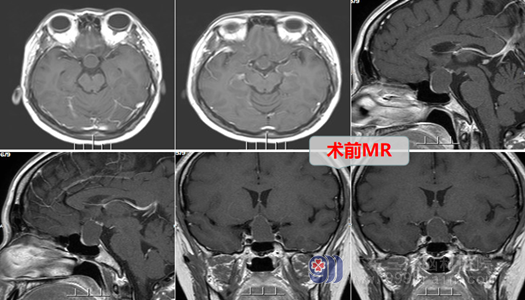

小银在七年前发现自己月经不规律,期间也有到医院寻医问诊,吃了药后也稍有好转,但就在一年前,小银觉得应该好得差不多了就自行停了药不吃了,可是,接下来左等右等月经就是不来了,这下小银可乱了神,自己结婚才刚过七年之痒,还没抱上小孩怎么就闭经了呢?就连忙到医院查了头颅MR发现是鞍区占位性病变,小银一时拿捏不好,在好朋友的介绍下,慕名来到了广东三九脑科医院找到了欧阳辉教授,欧阳教授耐心的接待了小银,查看了她的影像资料后解释道:“这是一种良性的病变,是一个囊肿,它压迫了正常垂体,经鼻微创手术即可解决问题,预后良好”,取得小银和其家属的同意后,欧阳辉教授团队在内镜下为小银进行了经鼻蝶鞍区Rathke’s囊肿开窗引流手术,手术进行得非常顺利,术后的小银也没有出现后遗症,激素水平逐渐恢复。我们也祝愿小银康复后能如愿怀上一个大胖小子。